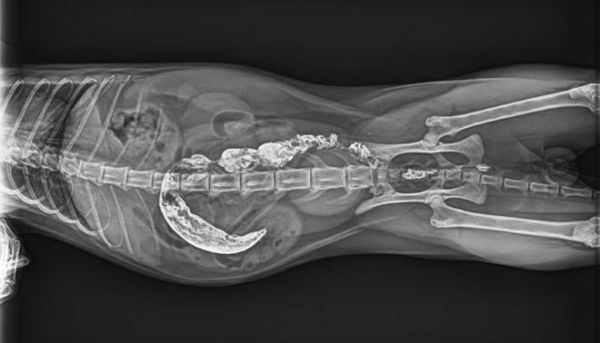

必康宠物DR以实测数据彰显高清硬实力:经线对卡实测,成像分辨率均值可达3.7lp/mm,峰值可达4.0lp/mm,远超行业常规标准,细微到0.1mm的骨骼裂纹、脏器微小结节,甚至是纤细如发丝的血管、豌豆大小的淋巴结,都能清晰可辨。临床应用中,无论是小型犬的隐匿性骨折、猫咪的早期骨裂,还是兔子上臼齿牙根异常生长压迫眼球的复杂病例,必康DR都能精准捕捉病灶细节,清晰呈现病变位置、大小与形态,帮助兽医快速锁定病因,为后续治疗筑牢诊断根基。

某宠物医院接诊一只精神萎靡、眼球突出的兔子,疑似严重牙科疾病,常规DR拍摄的影像模糊,无法清晰呈现齿根状态,难以确诊。借助必康宠物DR的高清成像与AI器官分割功能,设备快速捕捉影像,清晰呈现兔子右臼齿的过长、歪斜,以及齿根穿透牙槽骨、压迫眼球后方的细节,AI伪彩增强进一步凸显病变区域,兽医几分钟内便精准确诊,为后续手术治疗争取了宝贵时间,也让宠主看到了希望。